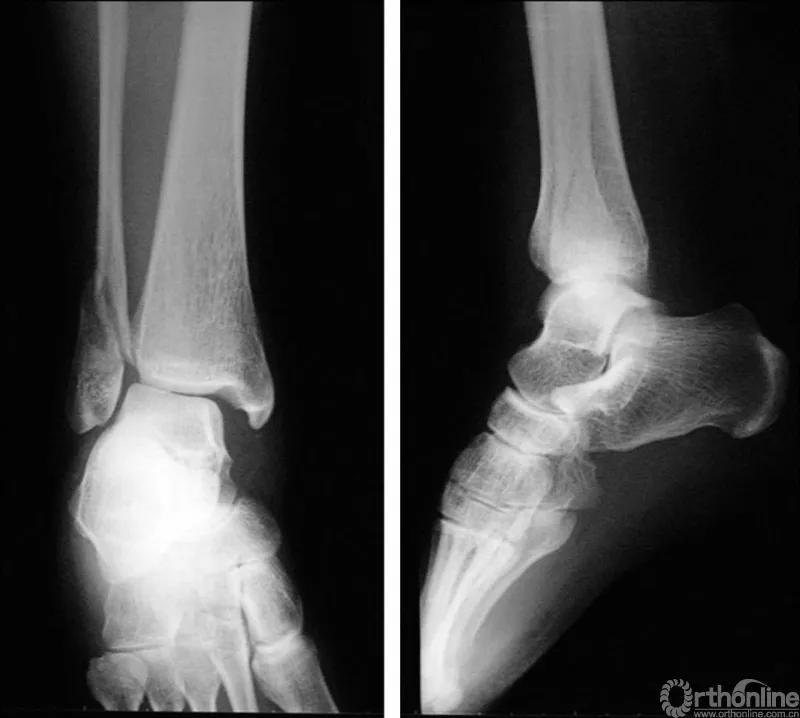

X线诊断:标准的踝关节影像学评估应包括3个位相:前后位(图5),踝穴位(内旋15°)(图6),侧位(图7)。

图5 前后位

图6 踝穴位(内旋15°)

图7 侧位

当踝关节严重损伤时内外踝及距骨将发生不同程度的移位(图8)。有时外踝骨折会伴有三角韧带的损伤,静态的X线摄片并不能准确地折射踝关节的稳定性,应力位片及MRI检查可完善对踝关节稳定性及韧带损伤的评估(图9)。此时应通过患肢损伤机制及放射资料准确判断踝关节损伤的类型以正确指导复位和固定。有时单纯内踝骨折可能是更为复杂的“Maisonneuve骨折”的一部分,该骨折还包括腓骨近端骨折及韧带联合损伤,故X线检查应投照整个胫腓骨。

图8 骨折移位明显合并有脱位